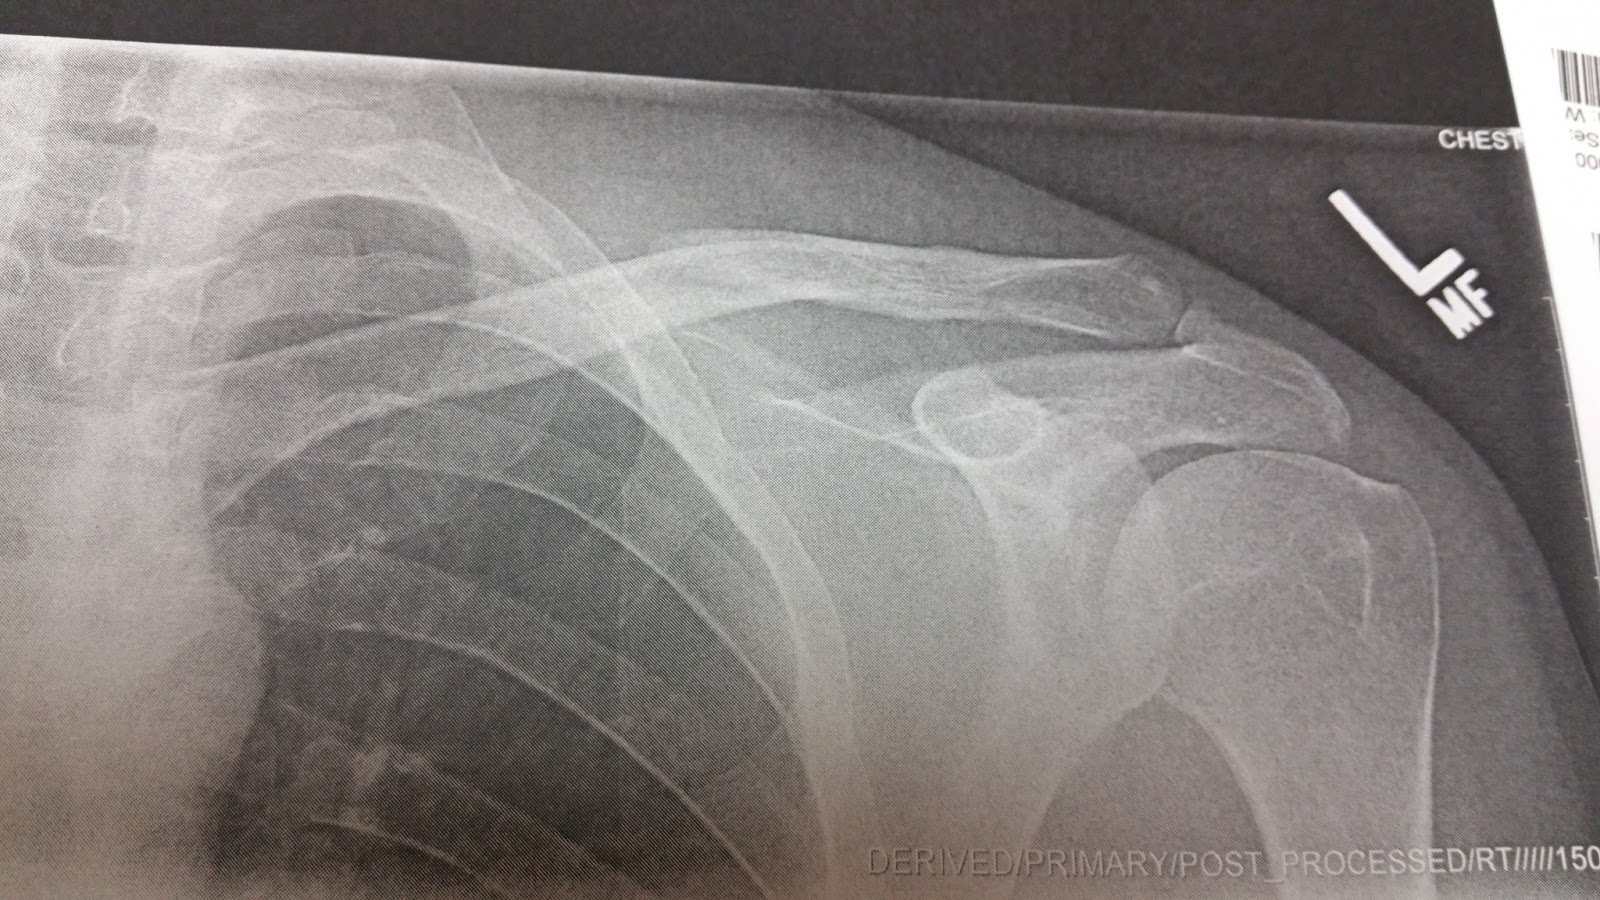

If you didn’t bust your collar bone over the weekend… like me… head on out to the Woolly tonight at 6pm for a group ride.